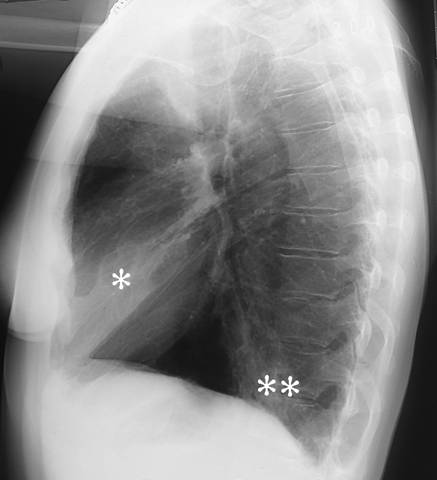

Lobar pneumonia (lateral view). Lobar pneumonia. The lateral radiograph shows alveolar consolidation both in the middle lobe (*) and in the inferior lobe (**) of the right lung. For PA view: see Lobar Pneumonia (Pa View).